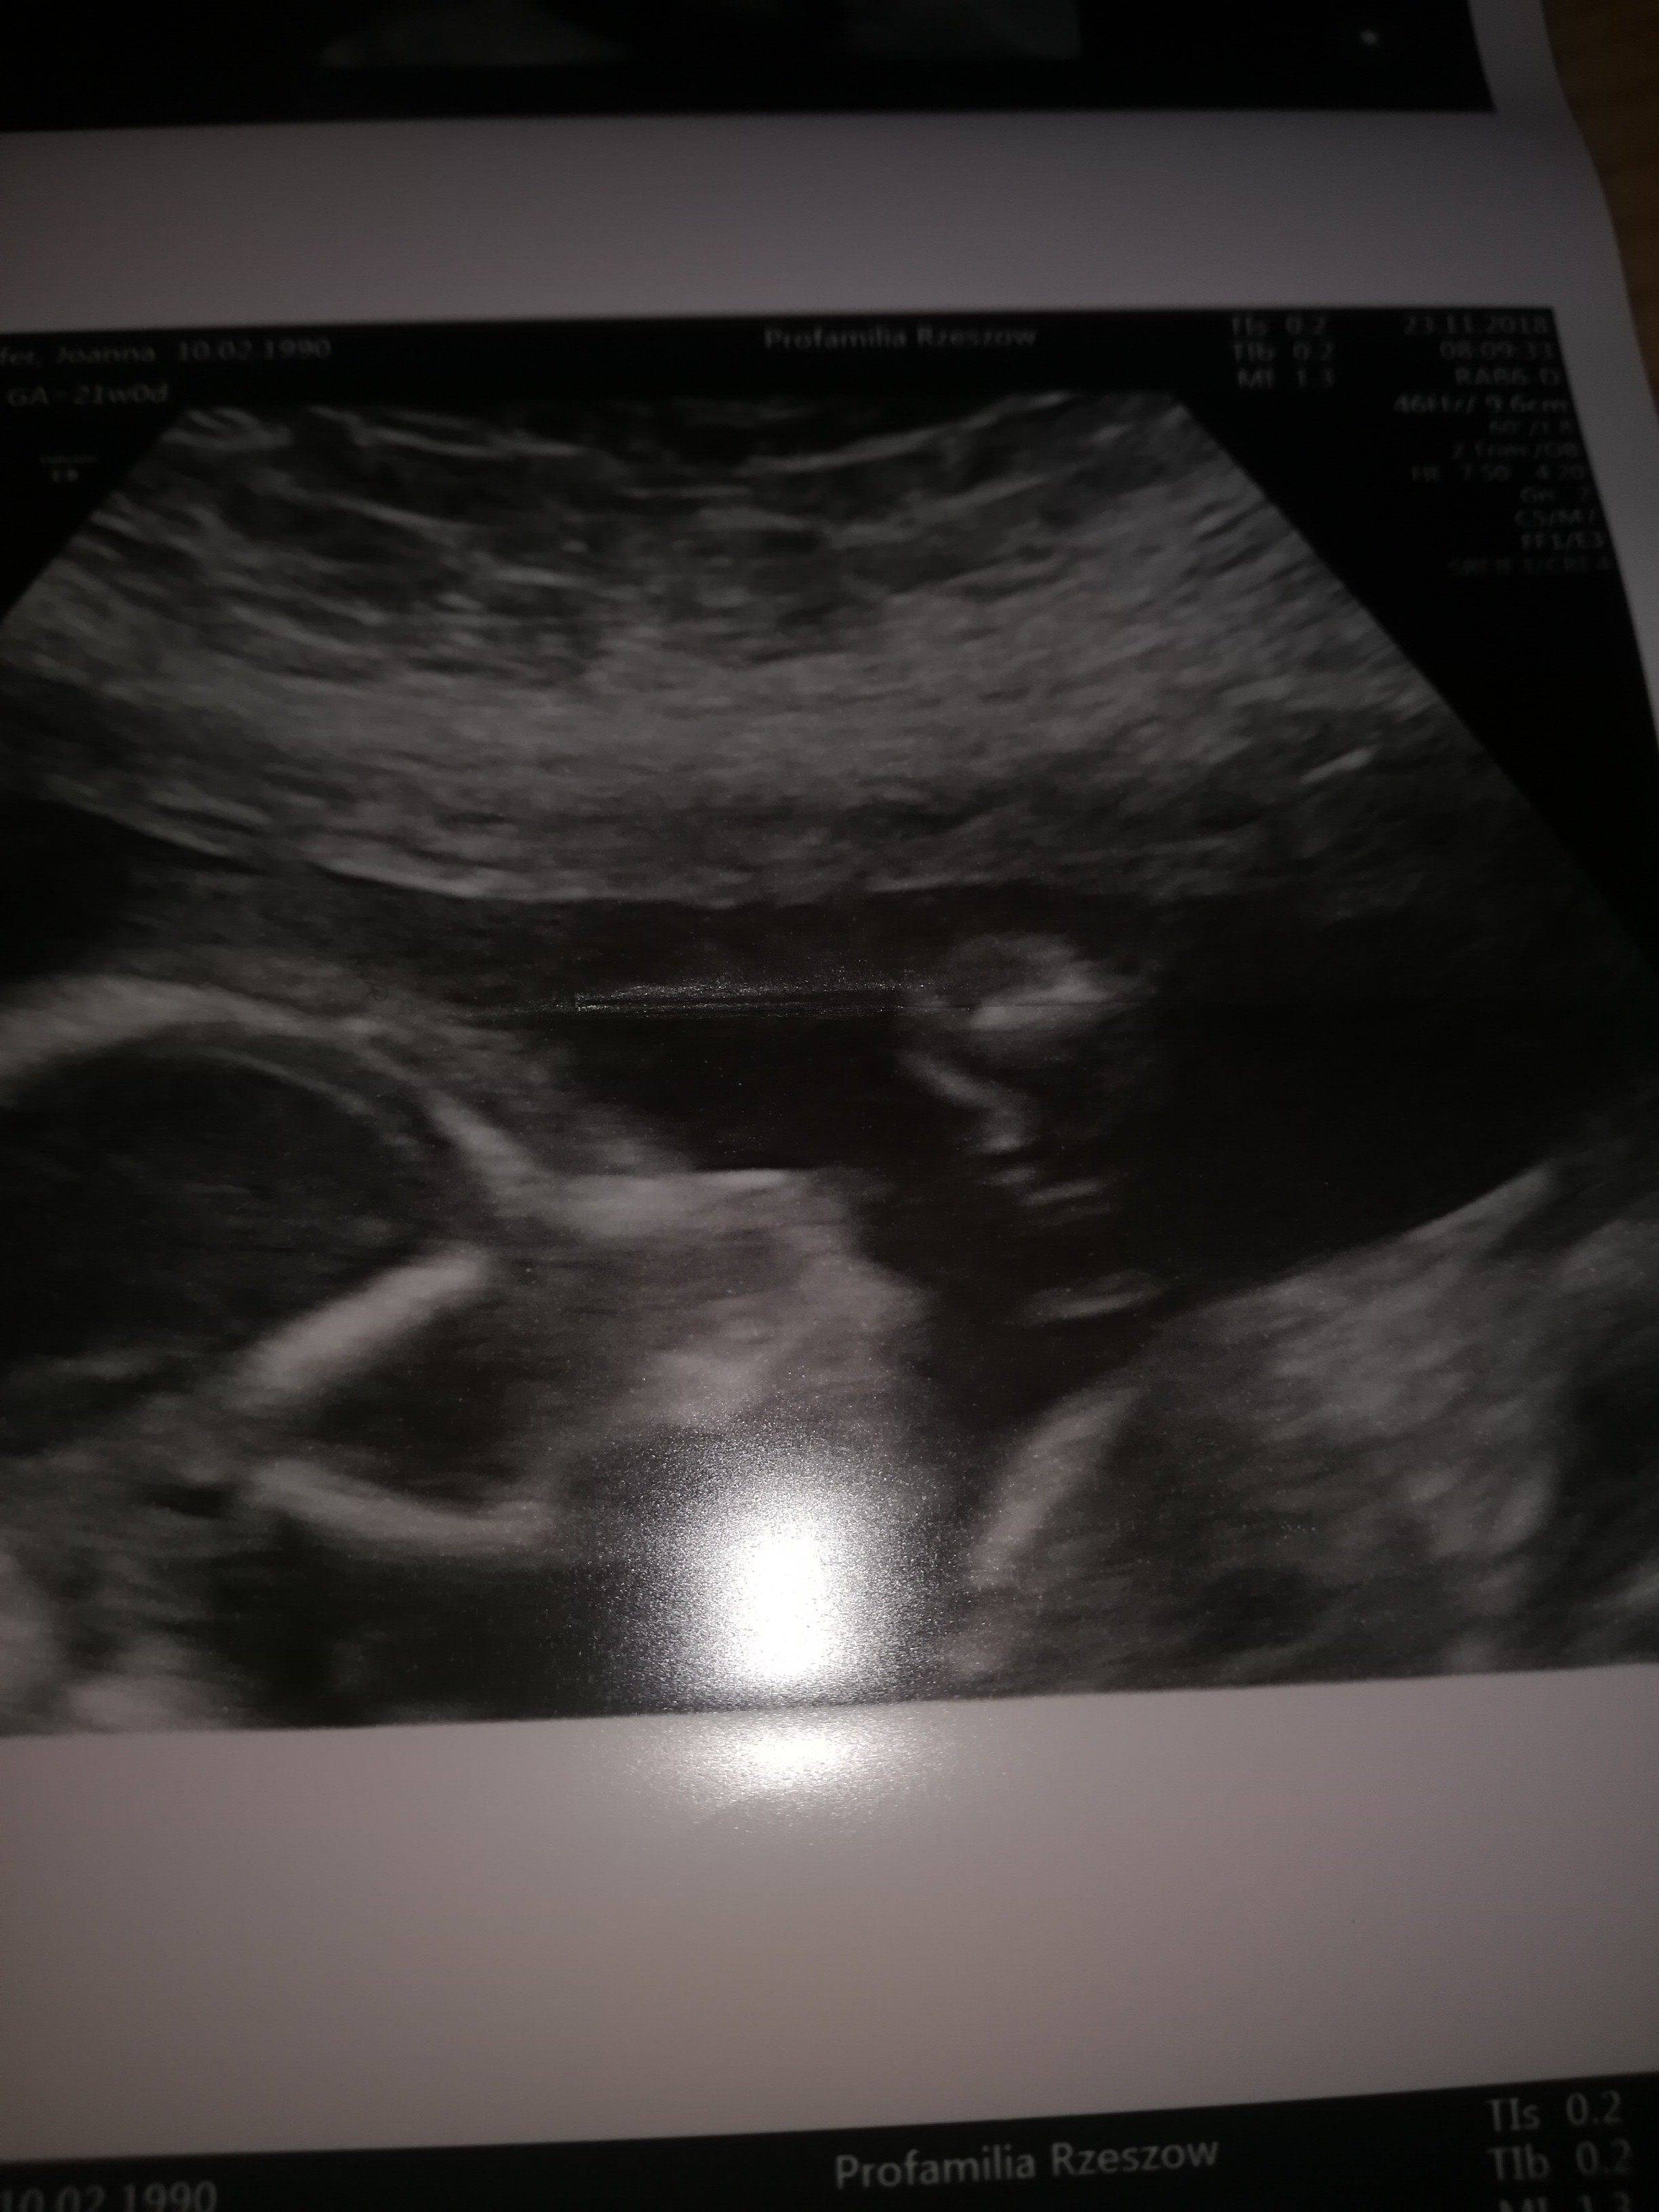

Połówkowe w poniedziałek 03.12 ☺ wszystko w porządku jednak w NL niewiele mówią mamy z mężem teraz wątpliwości bo przy prenatalnych wyszło że będzie chłopak teraz że dziewczynka a jeśli chodzi o mnie to ja nie widzę nic na tym zdjęciu Mamuśki może Wy się wypowiecie?;) a do wstawiam w załączniku

• 20181205_120533.jpg

20181205_120533.jpg

405,4 KB · Wyświetleń: 343